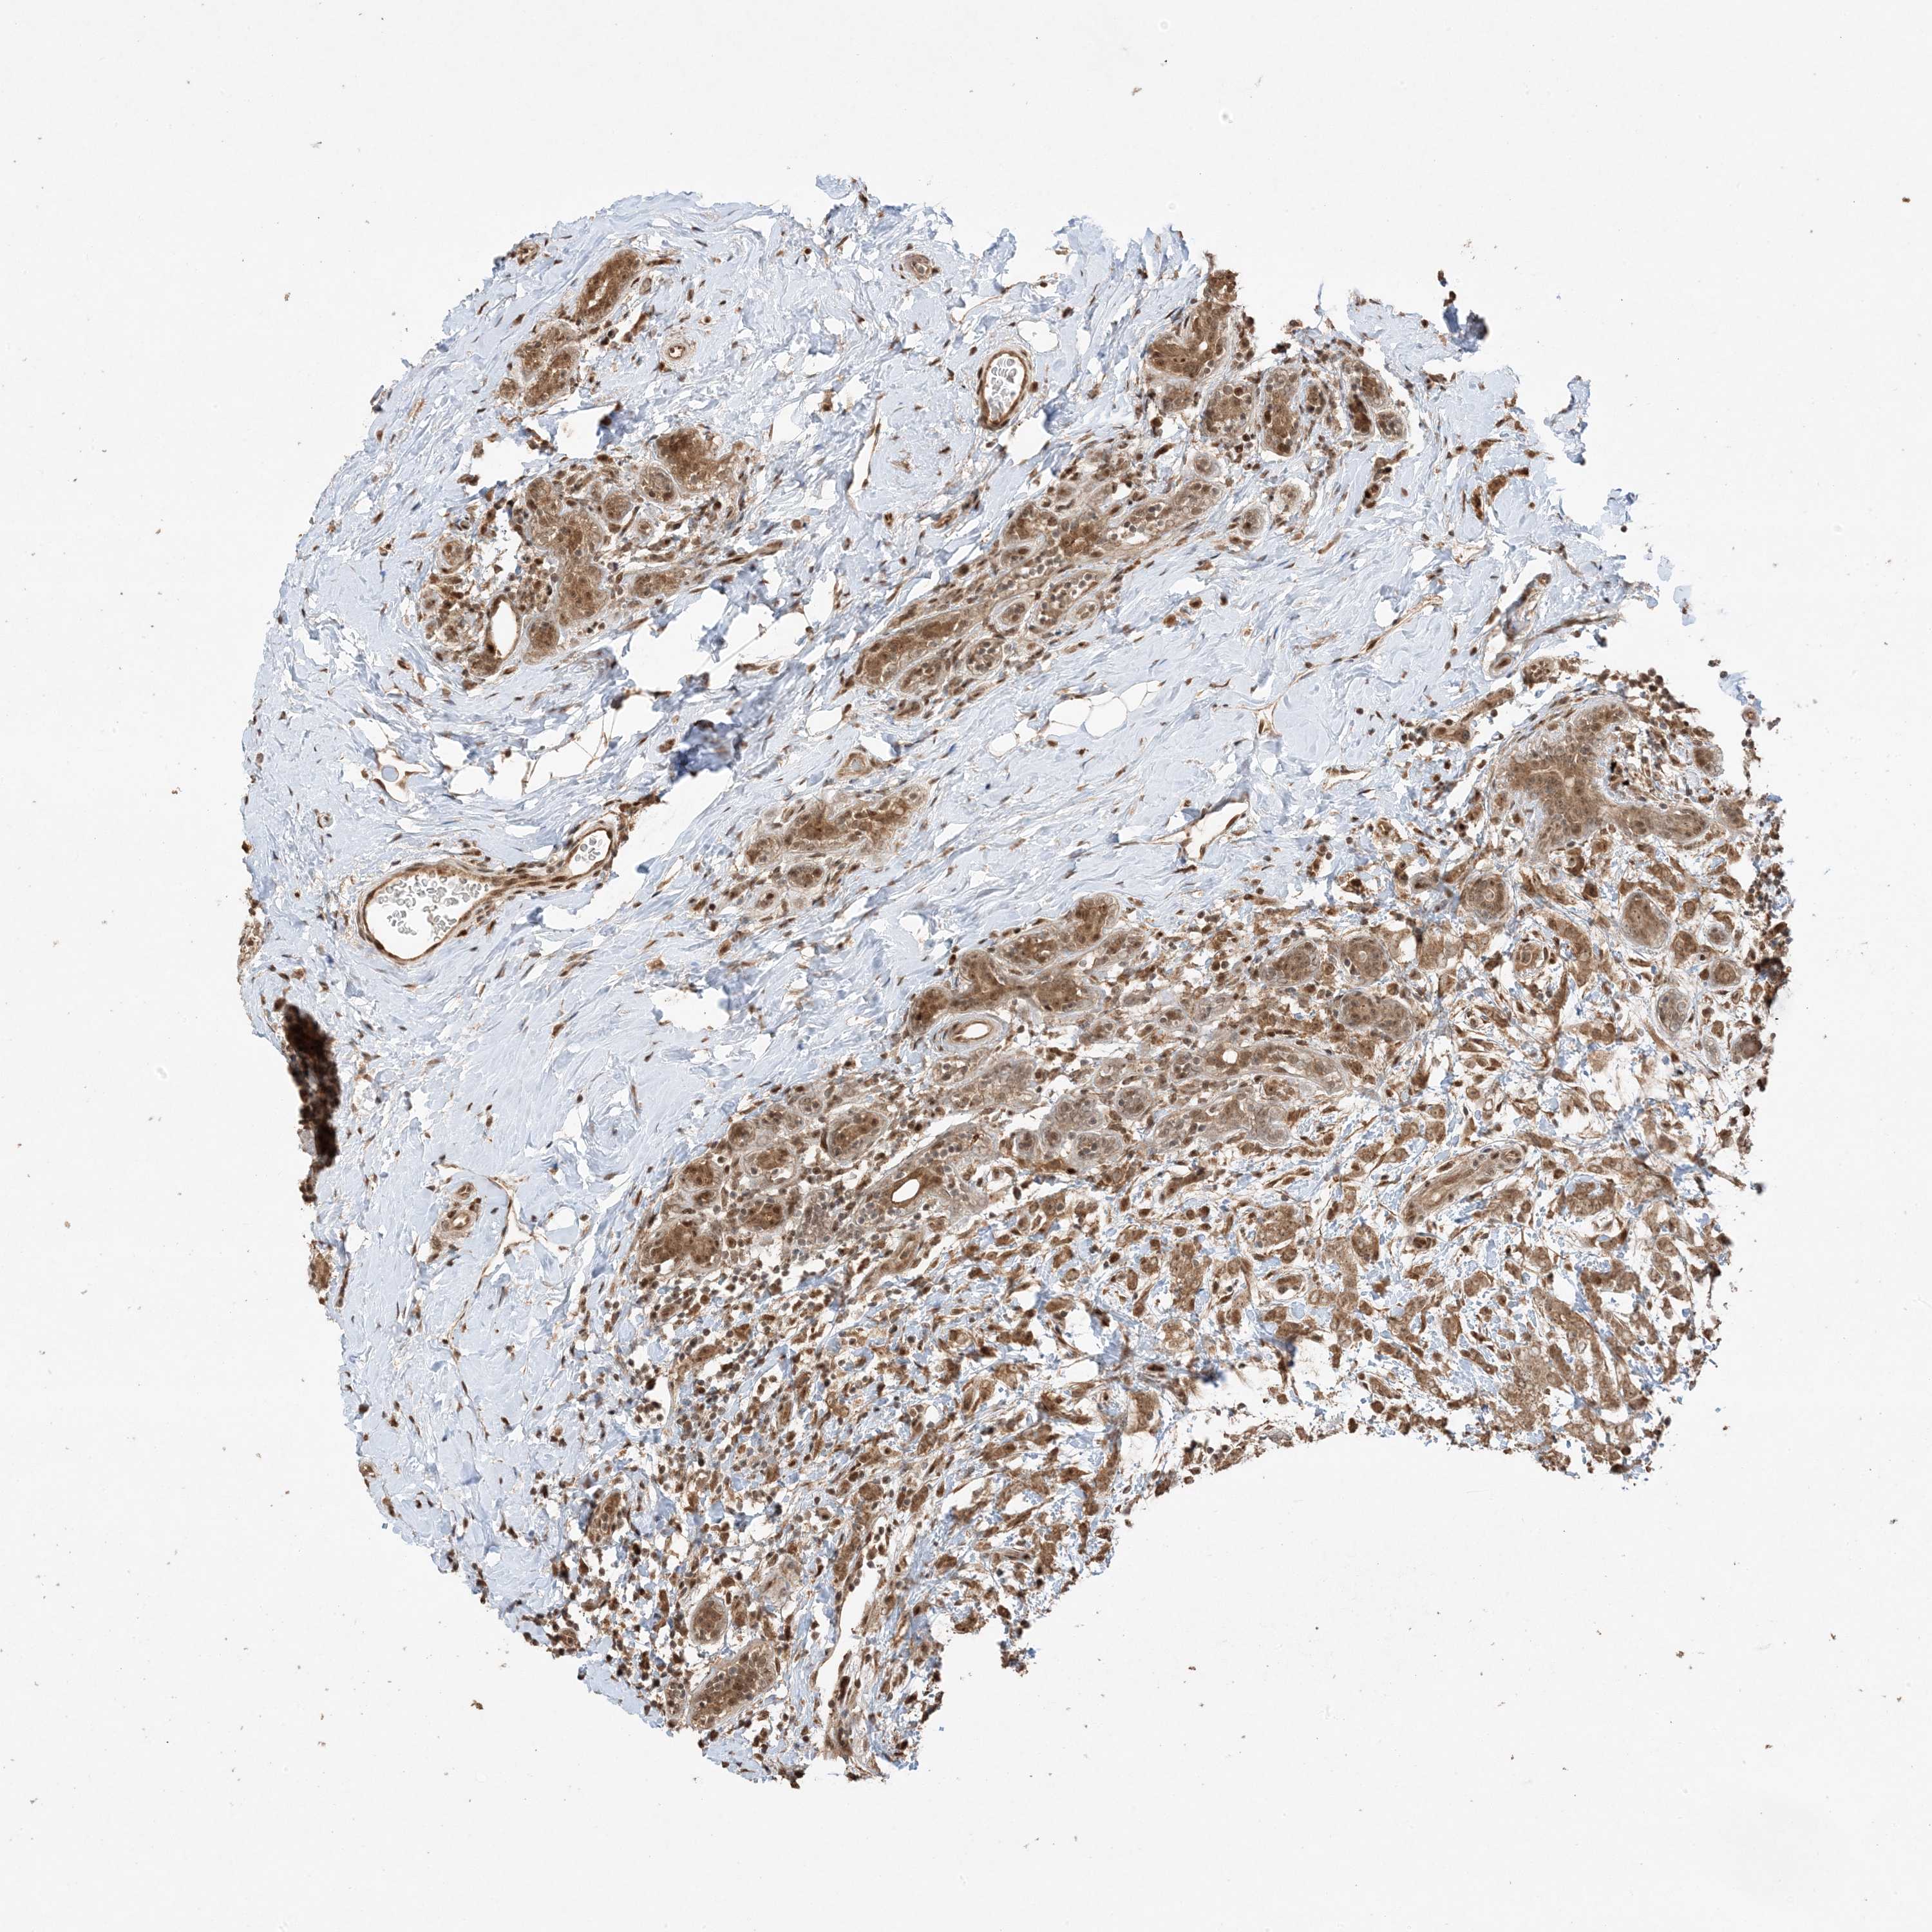

CANCER BREAST CANCER Show tissue menu

BRCA TCGA BRCA VALIDATION PROTEIN EXPRESSION